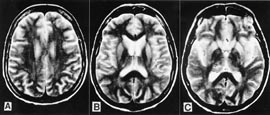

Pasienten. 54 år gammel kvinne. Hun hadde tidligere stort sett vært frisk, men gjennomgikk flere tannekstraksjoner og maksillærkirurgi det siste året før sykdomsdebut. De første symptomene var svimmelhet, asteni og vertigo, som tiltok gradvis. Åtte måneder senere utviklet hun ustø gange, eufori og raskt progredierende demens med desorientering, tap av korttidsminne og visuelle hallusinasjoner. Ved klinisk undersøkelse fant man nystagmus, ataksi, myoklonus, positiv mandibular og palmomental refleks og grav demens. Computertomografi (CT) av hjernen og blodprøver viste normale funn. EEG viste diffus dysrytmi med generalisert theta- og deltaaktivitet, men de typiske periodiske skarpe bølger som vanligvis sees ved Creutzfeldt-Jakobs sykdom, var ikke til stede. T2-vektet MR av hjernen viste ingen definitive avvik (fig 1). Diffusjonsvektet MR av hjernen viste markert økt signaldensitet, dvs. redusert diffusjon bilateralt i corpus striatum og gyrus cinguli (fig 2). Hun døde etter en måned i koma, 15 måneder etter debuten av de første symptomene. Diagnosen ble postmortalt bekreftet med utbredte, typisk spongiforme encefalopatifunn ved den histopatologiske undersøkelsen (fig 3). Prionproteingenanalyse viste ingen mutasjoner, men hun var homozygot for valin/valin i codon 129 (utført ved Creutzfeldt-Jakob Disease Surveillance Unit, Edinburgh, Skottland).